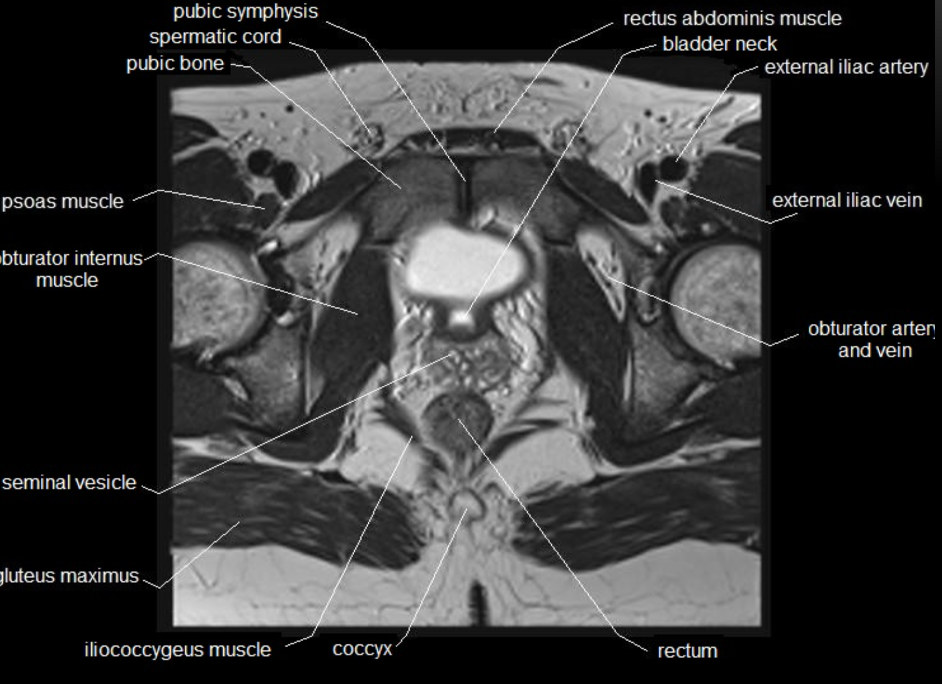

What type of imaging modality is this & fill in the blanks

MRI prostate, axial